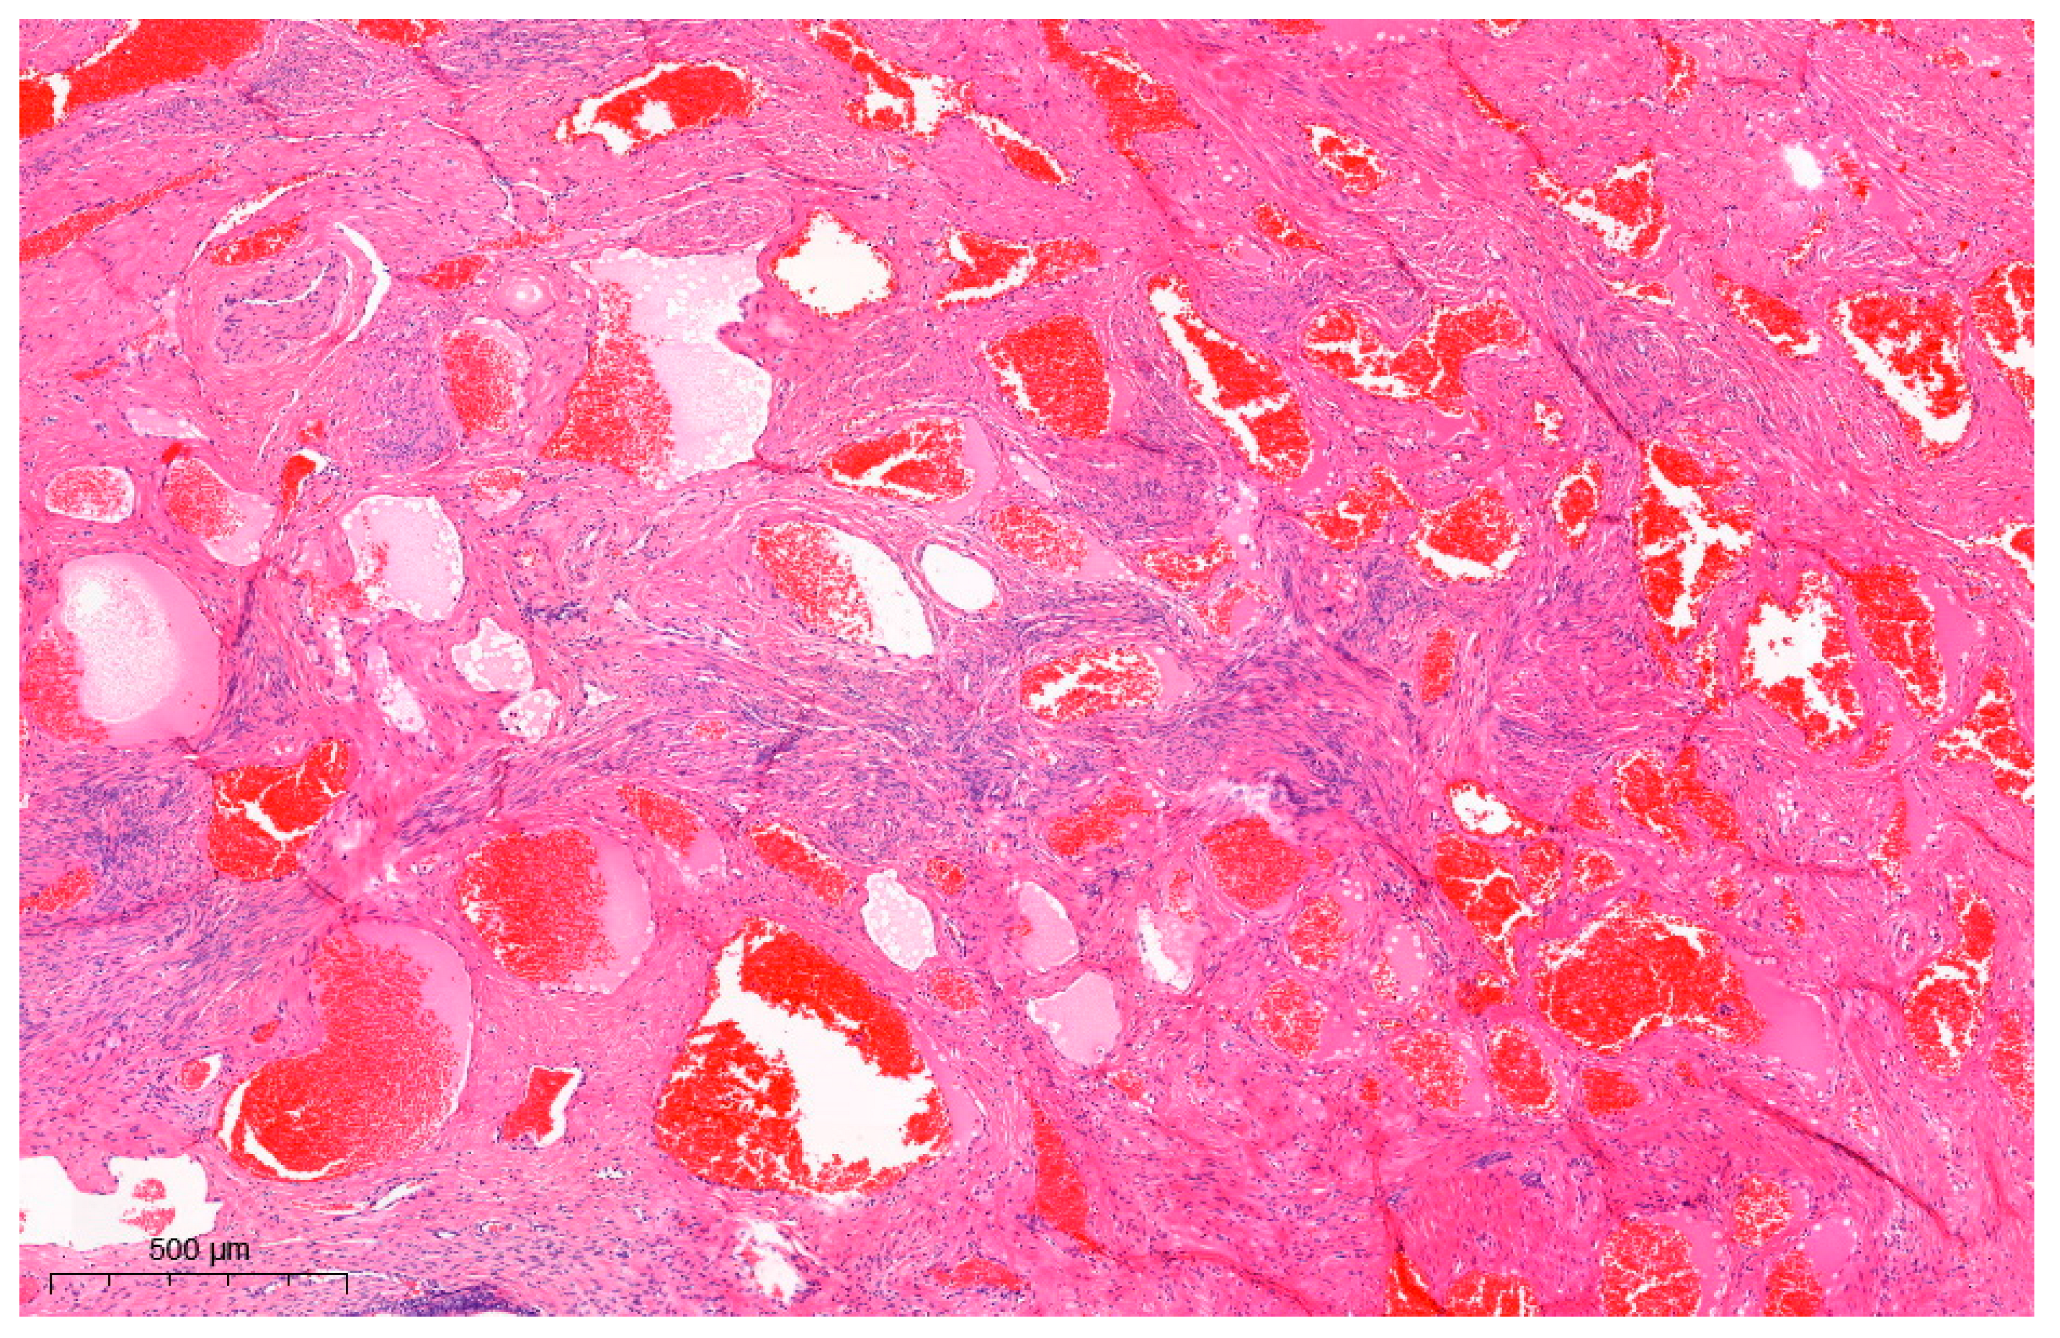

Uterine Cervical Angioleiomyoma Mimicking Squamous Cell Carcinoma